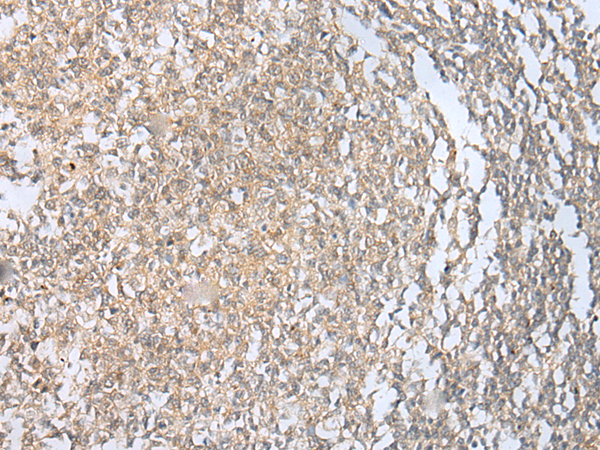

分类: 科研抗体货号: P11096别名: HRMT1L3应用: IHC反应种属: Human